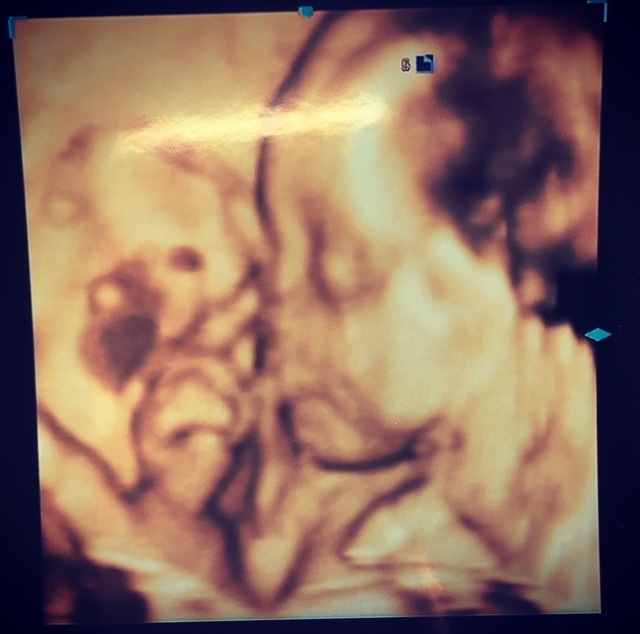

23週2日(23w2d・女の子)|BeaT09 さん(36歳)

エコー写真撮影時のエピソード:

いつもエコー写真の時に顔を隠してる恥ずかしがり屋さんの赤ちゃんだけど、この日は1人で何回も

いないいないばぁ

を繰り返してた時の写真です。

顔を隠してる時に腕の奥に目も確認できて嬉しかったし、 気付いたらこんなにも人間らしい顔になってて感動しました。